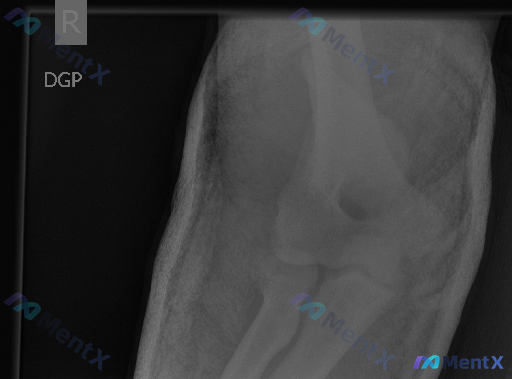

- 检查方式:右侧肘关节正位X光片

- 肱骨远端(外上髁、内上髁、小头、滑车)、尺桡骨近端(桡骨头、颈,尺骨冠突、鹰嘴)骨皮质连续,未见明确骨折线或移位

- 肱尺关节、肱桡关节、桡尺近侧关节对位良好,无脱位或半脱位

- 骨小梁清晰,无明显骨质疏松、溶骨或成骨改变;关节间隙宽度可,边缘光滑,无明显退变征象

- 周围软组织影轮廓可,无明显局限性肿胀或钙化(正位片难以评估典型后脂肪垫征)

- 初步影像评价:所检右侧肘关节骨骼结构完整,骨质未见明显异常,关节对位良好,未见明确骨折或脱位征象